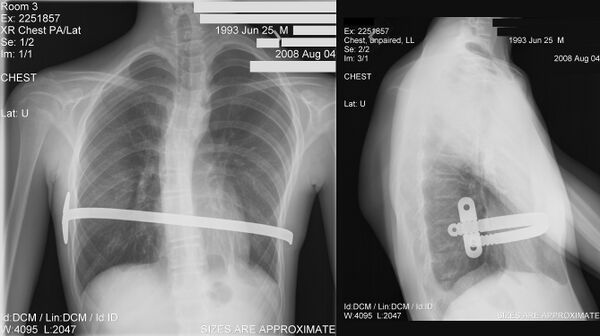

В ходе операции производится два небольших боковых разреза с обеих сторон грудной клетки. Через отверстие вводят интродьюсер, который проводят сначала в подкожное пространство, под мышцы, внутрь грудной клетки и за грудину, далее проводится перед перикардом в сторону противоположному разрезу кожи. Процесс можно контролировать с помощью торакоскопа. К интродьюсеру фиксируют тесьму и производят извлечение интродьюсера. По ленте вдоль сформированного канала проводится специальная титановая или стальная пластина (обычно её вводят с правой половины грудной клетки). Когда пластина введена и корректно размещена, её поворачивают. Заключительный этап операции — фиксация и стабилизация пластины — это делается нескольким способами — подшиванием к рёбрам и мышцам, установлением специальных фиксаторов (по Парку) или с использованием стабилизаторов (классически по Нассу или по Пилегарду).